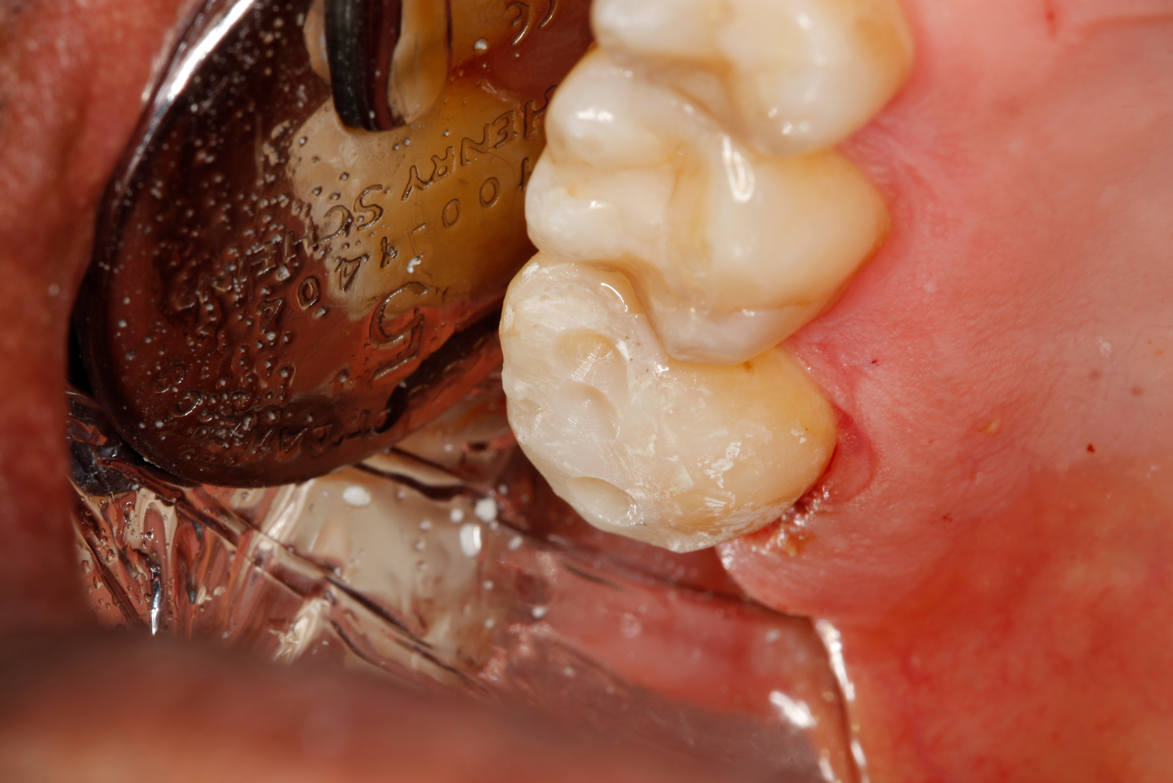

Fig 9. View of existing occlusal composite to be removed to access the distal lesion on tooth No. 2.

Figure 9

Figure 8A is a radiograph revealing deep root caries previously restored temporarily by a resident at the AEGD Residency Program clinic with glass ionomer utilizing a lateral rather than occlusal approach. After the glass ionomer failed to adhere, another resident again attempted a lateral approach that resulted in the restoration shown in Figure 8B. A third resident had success with an occlusal approach, removing a failed occlusal composite to access the distal  (Figure 9). This attempt was successful both in the preparation of the lesion and in the placement of a dual- cure bulk-fill flowable (Bulk EZ Plus, Zest Dental Solutions; alternatively: HyperFIL®, Parkell; Fill-Up!, Coltene) extruded through a bendable needle (Figure 10). Figure 11 shows the final preparation after tissue removal was accomplished with rotary gingitage; note that this was performed with the rubber dam in place. An air abrasion device (Groman Etchmaster, Groman Dental; alternatively: PrepStart H2O, Zest Dental Solutions; Bioclear Blaster, Bioclear) was used with potassium bicarbonate to remove biofilm prior to acid etching (Figure 12). Phosphoric acid 37% was utilized in a total etch fashion (Fig- ure 13 and Figure 14) for 20 seconds. Figure 15 shows the universal bond (Scotchbond Universal, 3M; alternatively: All-Bond Universal®, BISCO; Prelude One, Danville Materials) with metha- cryloyloxydecyl dihydrogen phosphate (MDP) being scrubbed into the cavity for 20 seconds. After air thinning for 20 seconds, the adhesive was light cured for 40 seconds at 1,200 mw/cm2power density (Figure 16).